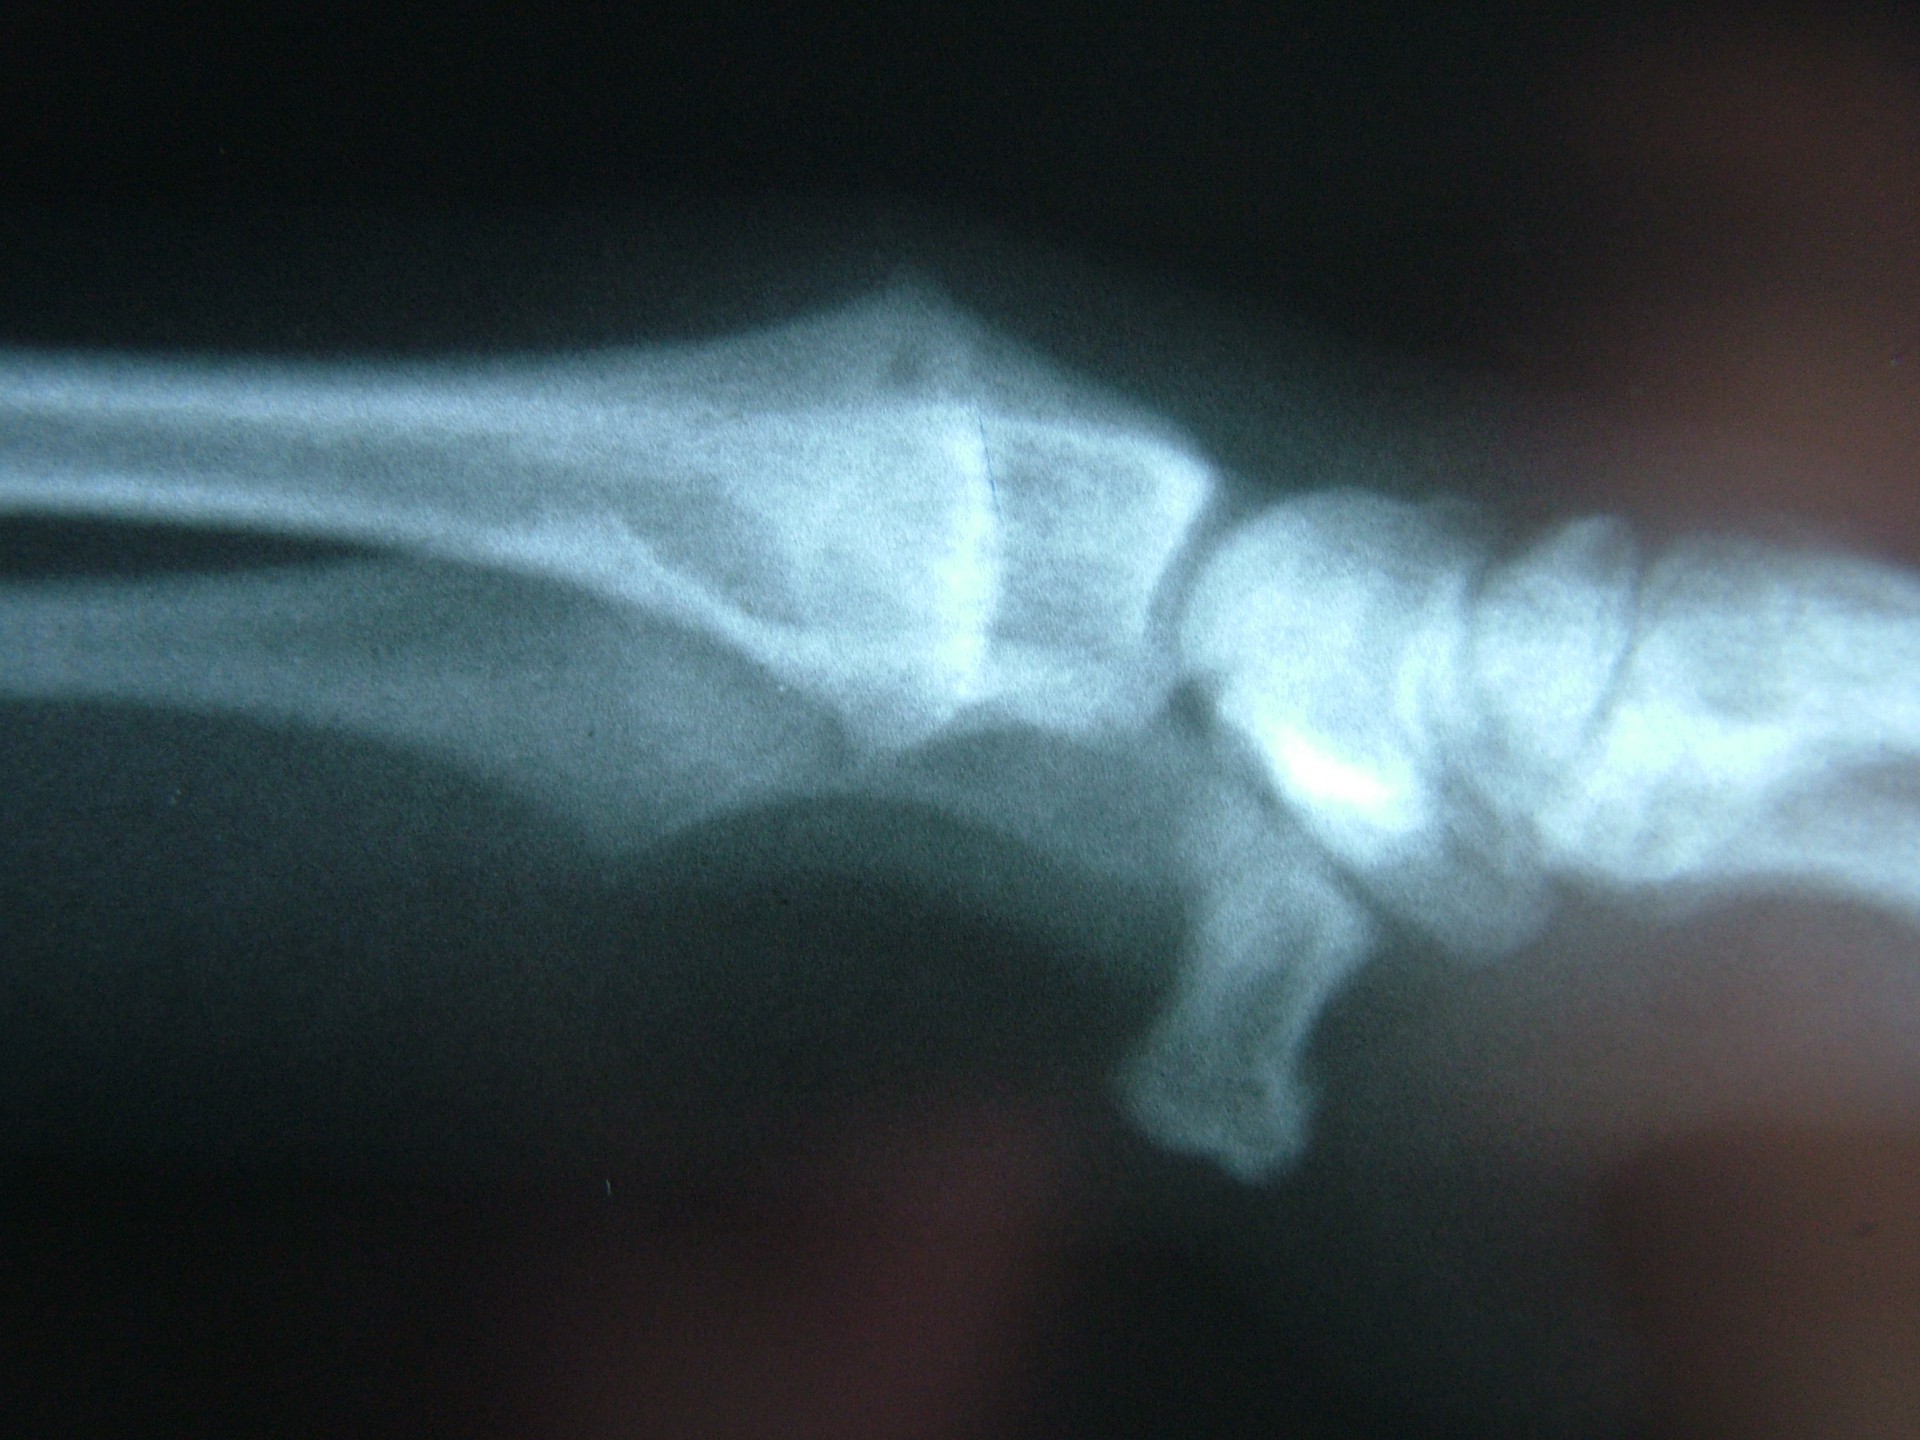

Az alkarcsont növekedési zónájának záródása (short radius)

Az alkarcsont növekedési zónájának záródása általában a könyökízületben un.: inkongruenciát okoz. A könyökízület működéséhez az azt alkotó 3 csont (karcsont, könyökcsont, alkarcsont) tökéletes illeszkedése elengedhetetlen. Azokban az esetekben amikor bármely 2, a könyökízület alkotásában résztvevő csont ízületi felszíne nem illeszkedik tökéletesen,rendellenes ízületi alakulásról, inkongruenciáról beszélünk. Ezekben az esetekben az ízületi felszínek nem megfelelő terhelődése azok kopásához, idült ízületgyulladáshoz, következményesen fájdalomhoz vezet.

Az alkarcsont alsó vagy felső növekedési zónájának lezáródása esetén a könyökízületben kialakuló inkongruencia az ízület mozgásának fájdalmasságához, a mozgáspálya beszűküléséhez vezet. Paradox módon az ilyen elváltozás esetén is (mivel az alkarcsont a teherviselő csont) a könyökcsont osteotomiájával, annak növekedésének korlátozásával gyógyítjuk a beteget.

Az idejében észrevett elváltozás esetén, - amennyiben a csövescsontok növekedése még nem állt le -, az ízület normalizálódik, az eredeti funkció visszaáll.Súlyos fokú inkongruencia kialakulása esetén az ízületi funkció már nem állítható vissza. Azokban az esetekben, amikor a súlyos ízületi elváltozás fájdalommal jár az ízület bemerevítésével (arthrodesis) a fájdalom megszüntethető.